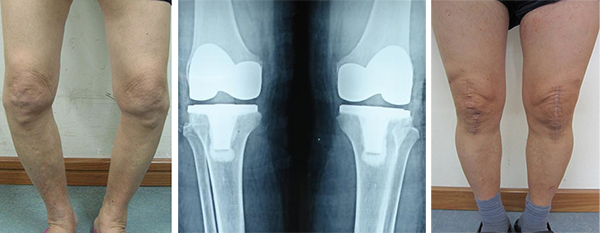

3、双侧膝关节置换技术

2003年在峡市率先开展人工膝关节置换治疗重度骨性关节炎,术后关节疼痛症状、活动功能恢复正常,治疗效果十分满意。目前在峡市该手术技术以引进和开展早,手术数量多,社会影响力大,处于绝对技术优势。